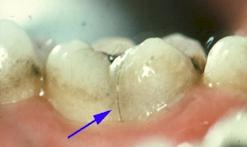

Il en va de même pour une fêlure qui aboutira à la fracture.